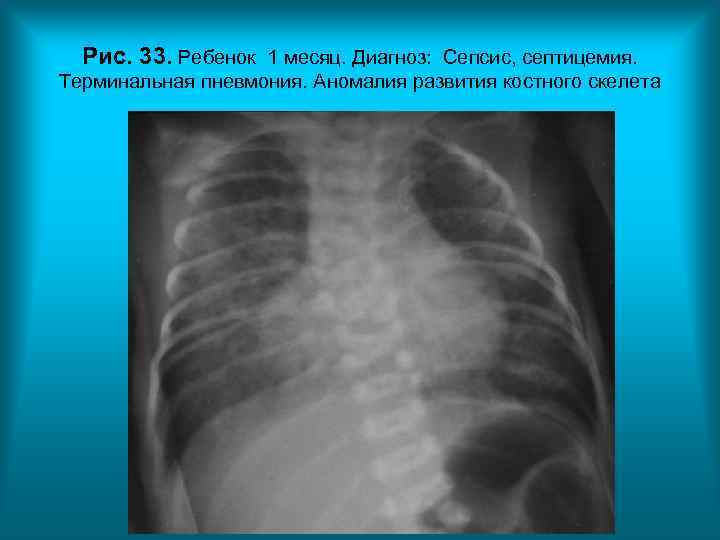

Рис. 33. Ребенок 1 месяц. Диагноз: Сепсис, септицемия. Терминальная пневмония. Аномалия развития костного скелета Н. С. Воротынцева. С. С. Гольев Рентгенопульмонология